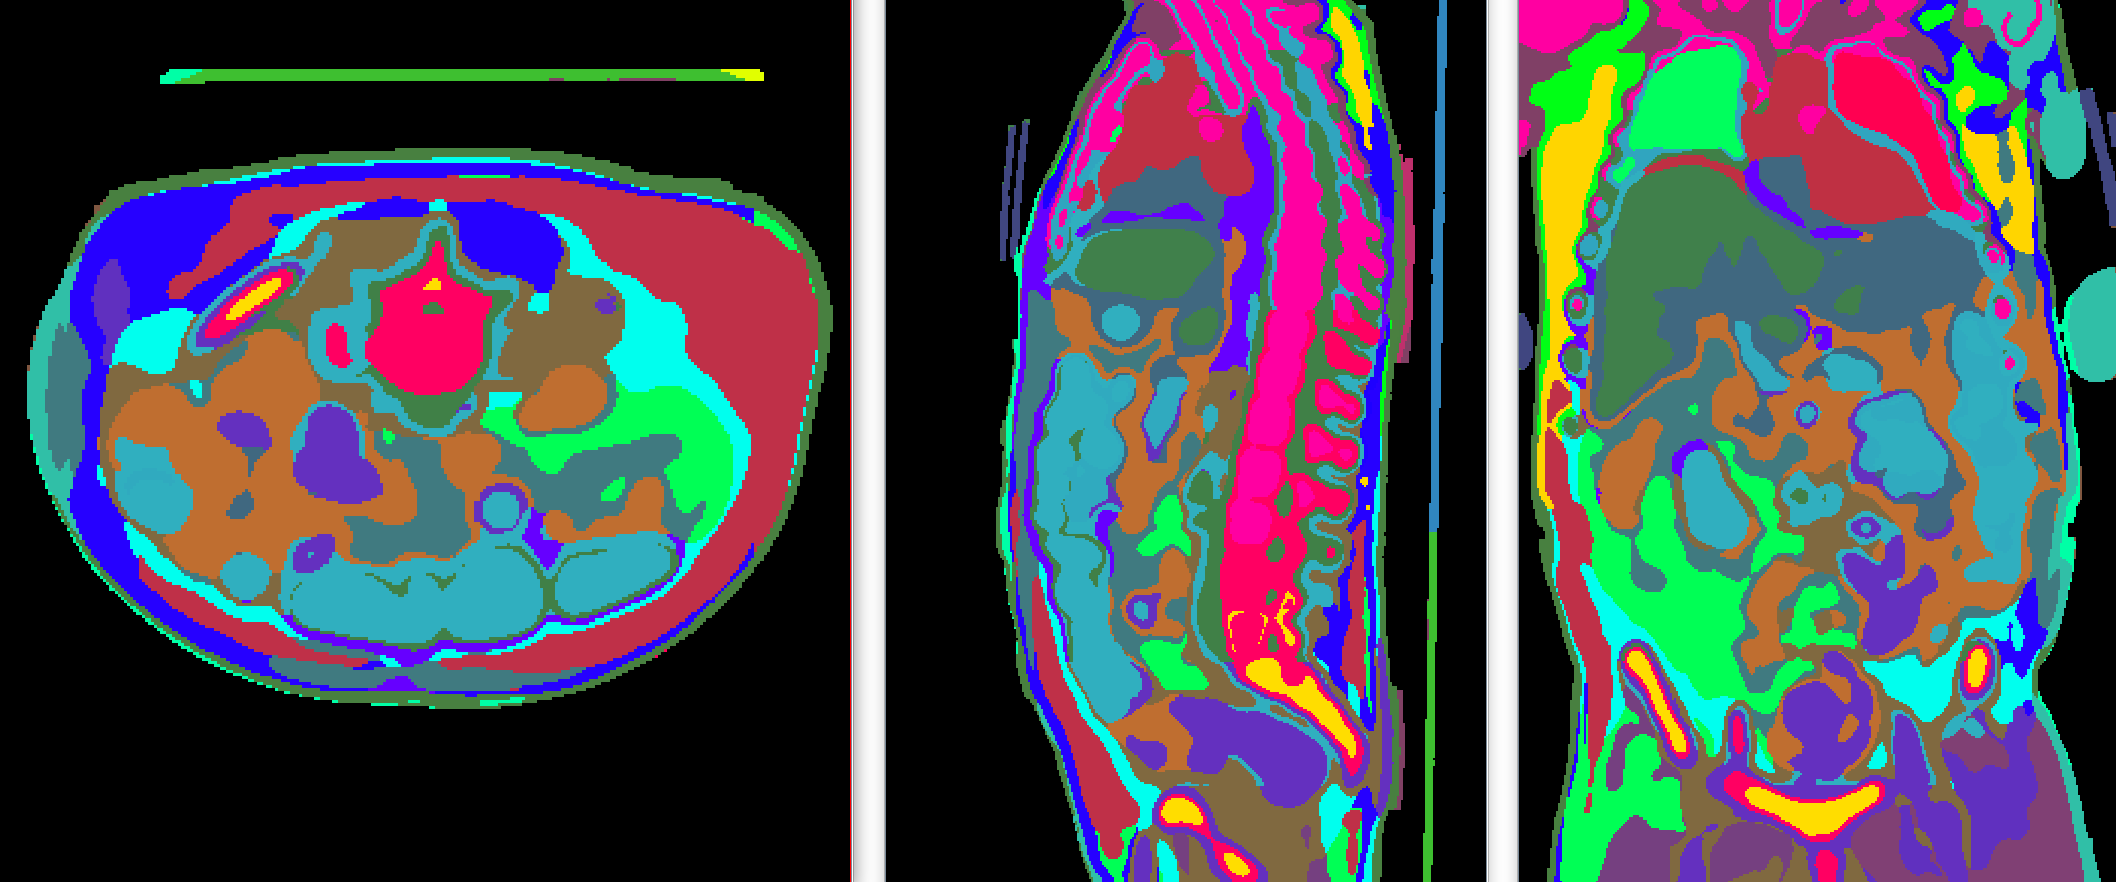

Supervoxel generation The vast majority of SAM’s zero-shot capabilities come from this large-scale supervised training on its 11 million diverse and fully annotated images [24]. Those annotations helped SAM learn how humans perceive an object, and become the image segmentation foundation model. However, the manual labels or pseudo-labels in 3D CT can only cover around one or two hundred of classes. We empirically found that this level of class diversity is not enough for the model to achieve SAM-like zero-shot ability in 3D. To solve this problem, most works decided to finetune SAM pretrained ViT checkpoint on 2D medical data to inherit this zero-shot ability, which inevitably limited the adaptability to 3D images. Here we propose a novel method to distill the image understanding ability from SAM by generating 3D supervoxels from 2D SAM feature maps. The algorithm is shown in Alg. 2. We perform a 3D supervoxel algorithm on the upsample SAM feature embedding, which is generated slice-by-slice in three views. An example of generated supervoxel results is shown in Fig. 2. We generate supervoxels for all 11454 CT scans and use them to train our interactive branch, and this gave VISTA3D zero-shot capabilities. SegVol [14] used a similar idea but the supervoxel generation is based on graph-cut, which is still on low-level image features. Instead, VISTA3D achieved better zero-shot performance through distilling knowledge from SAM.

In this section, we test the zero-shot ability of VISTA3D. We compare with MedSAM [28] and SegVol [14] as they showed the best interactive performances in 2D and 3D separately. For the MedSAM baseline, we adopt the 3D inference pipeline via a series of 2D slices as described in [28]. For segmentation targets that are larger than 10 voxels, tight bounding boxes for each slice were generated to simulate user-provided prompts. Each bounding box is considered the same annotation effort as two-point prompts in our evaluations. For the SegVol baseline, the default settings [14] are evaluated using a positive point with three pairs of positive and negative points (7 points in total), as well as the zoom-out-zoom-in inference strategy. For VISTA3D, We mimic user annotations to perform iterative point clicks. The first point is sampled at the foreground center, then the next point will be randomly sampled from the largest connected false positive or false negative region, which has a larger area size. We evaluate the performance of 4 novel external datasets. 1) the murine dataset [29] includes 140 scans with 4 annotated mouse organs: heart, left lung, right lung, and spinal cord. The CT scanning protocol and organ shapes are quite different to humans as shown in Fig. 3. 2) the C4KC-KITS (kidney tumor, 210 scans) dataset [18], the Adrenocortical Carcinoma (adrenal tumor, 53 scans) dataset [30, 13], the Hepatocellular Carcinoma (liver tumor, 105 scans) dataset [31, 13]. The results are shown in Fig. 3. The results show the superior performance of VISTA3D in both accuracy and reduced annotation efforts. VISTA3D trained without supervoxel (VISTA-NoSupervoxel) is also shown in the figure, and the results showed the importance of supervoxel for the zero-shot ability.